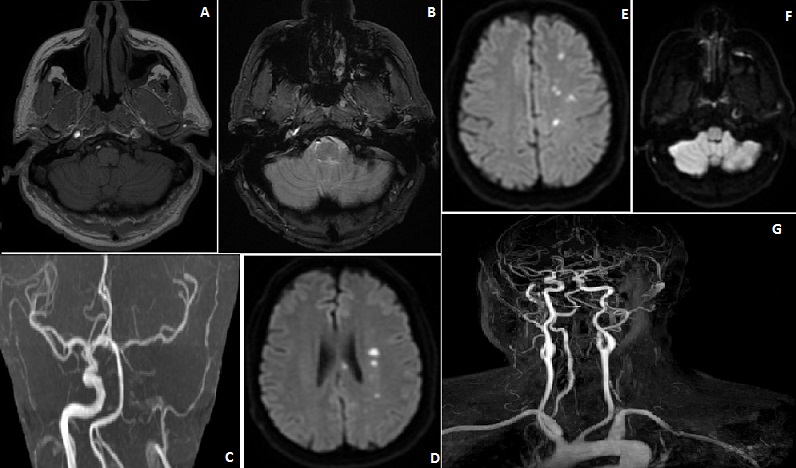

Les dissections des artères cervico-encéphaliques représentent la principale cause d'accident vasculaire cérébral (AVC) chez l'adulte jeune. Nous rapportons le cas d'un homme de 59 ans qui consultait pour une céphalée d'allure migraineuse avec des scintillements de l'œil gauche et une paresthésie de l'hémicorps droit paroxystique et d'évolution régressive. Chez un patient hypertendu et migraineux où l'examen clinique a permis de trouver une paraphasie phonémique avec manque de mots. L'imagerie par résonance magnétique (IRM) encéphalique en séquence vasculaire a montré en un hypersignal périvasculaire de l'artère carotide interne gauche (partie intra pétreuse) en diffusion et hyposignal en T2*, en faveur d'un hématome de la paroi avec occlusion artérielle à ce niveau. Aussi, plusieurs hypersignaux ponctiformes ont été mis en évidence en diffusion et Flair au niveau territoire artère cérébrale antérieur gauche et jonctionnel entre l'artère cérébrale antérieur et moyenne gauche sans présence de microbleeds au niveau parenchymateuse, en faveur d'un AVC d'origine embolique suite à la dissection carotidienne. Une anticoagulation à dose curative par antagoniste du vitamine K a été mise en place (INR cible entre 2 à 3) après héparinothérapie avec une rééducation orthophonique. Une angio-IRM tronc supra aortique à 3 mois a montré une reperméabilisation de La Carotide interne gauche intra pétreuse. L'imagerie est d'un intérêt majeur dans la confirmation diagnostique des dissections des artères cervico-encéphaliques et de l'éventualité d'un accident cérébral ischémique mais aussi thérapeutique tant immédiate que pour la suivi de ses patients.